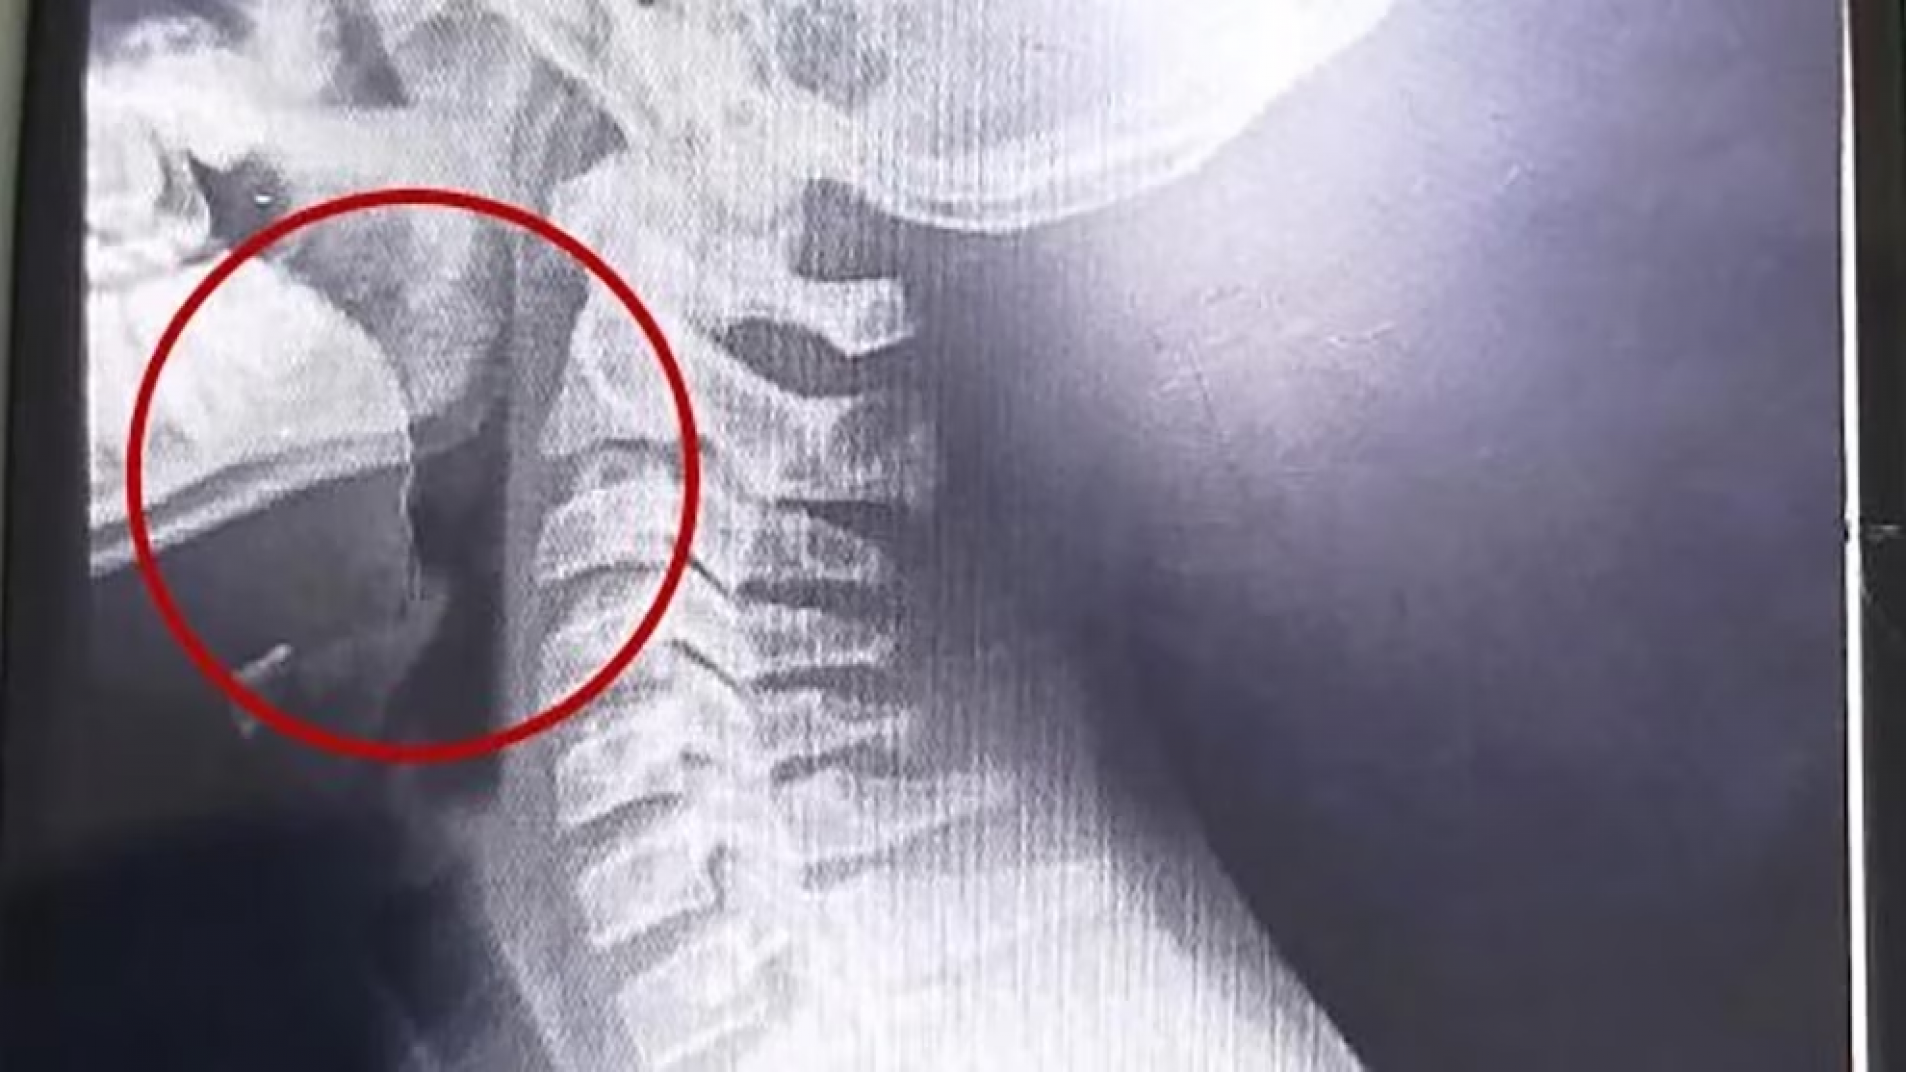

Mediante estudios por imágenes se halló un alambre fino incrustado en la garganta del paciente.

A continuación, se desarrollaron distintos estudios para descartar la presencia de infecciones o bacterias, cuyos resultados resultaron negativos. La clave para entender el cuadro apareció tras la realización de estudios por imágenes: las placas evidenciaron la presencia de un objeto extraño alojado en la vía aérea superior.

El parte médico consignó que el paciente ingresó "clínica y hemodinámicamente estable, afebril, vigil, reactivo, normohidratado y normoperfundido", según el medio local. Luego de una interconsulta con el servicio de otorrinolaringología, se resolvió su ingreso urgente a quirófano. Allí, el equipo médico halló un alambre fino incrustado en la garganta del adolescente, situación que no había sido advertida previamente.